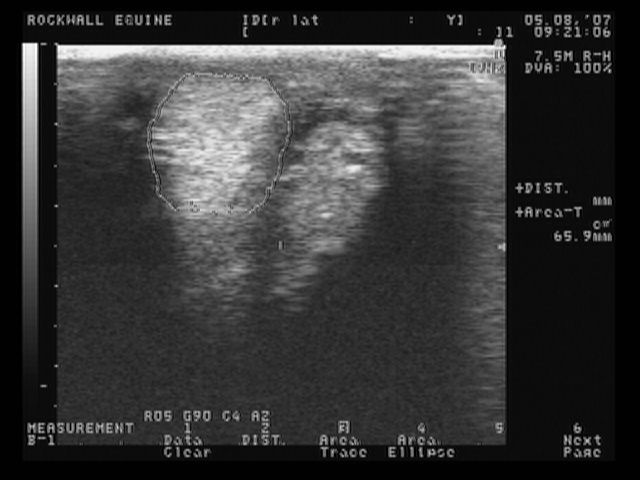

right lateral front

These are the most recent ultrasound images of my horses legs, done about 2 weeks ago. The original injury was in January, so he is about 4 months into healing. The left lateral is normal.